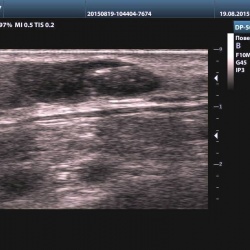

Женщина пришла на обследование мягких тканей коленного сустава. В процессе обследования, в подколенной ямке левого коленного сустава, было выявлено округлое анэхогенное образование, имеющее...